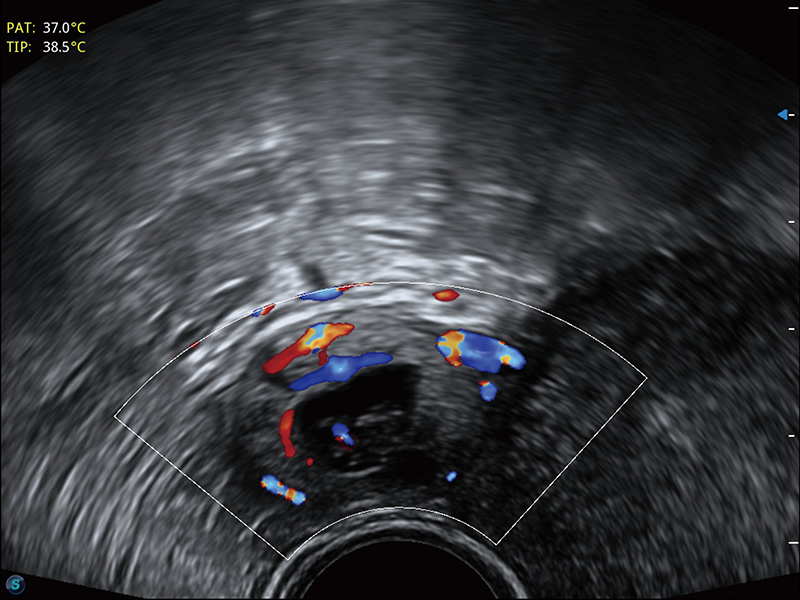

“生育问题”即关系民族复兴,也关系亿万家庭的幸福。随着婚育年龄推迟、社会压力增加等因素,越来越多人群也面临着“生不出、生不好”的问题。辅助生殖作为治疗不孕不育最有效的方法之一,也逐渐成为育儿新希望。而超声检查能为生殖需求人群的初诊评估提供宝贵的信息。 P20 Elite是哈哈体育官网匠心打造的一款生殖应用型彩超。她继承哈哈体育官网高端极光平台,突破性地将多款新型芯片及硬件模块进行整合,均衡了高端系统性能与小巧灵动机身。P20 Elite卓越的图像质量搭载专科探头,旨在为您提供全面的辅助生殖解决方案。

P20 Elite配备了丰富的生殖探头群和临床应用功能,在卵泡监测、穿刺取卵、胚胎移植、妊娠确认等领域,为生殖需求人群提供了新的临床机会,重新定义高端超声如何应用于生殖健康检查。